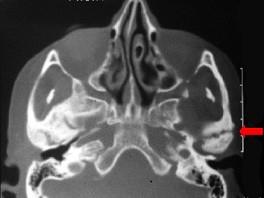

问题 患儿,5岁,外伤后逐渐出现张口困难,咬合关系错乱,髁突动度减弱,外观及X?线检查结果如图。最可能的诊断是()

选项 A.上颌骨骨折 B.下颌骨骨折 C.颧骨骨折 D.颧弓骨折 E.颞下颌关节强直

答案 E